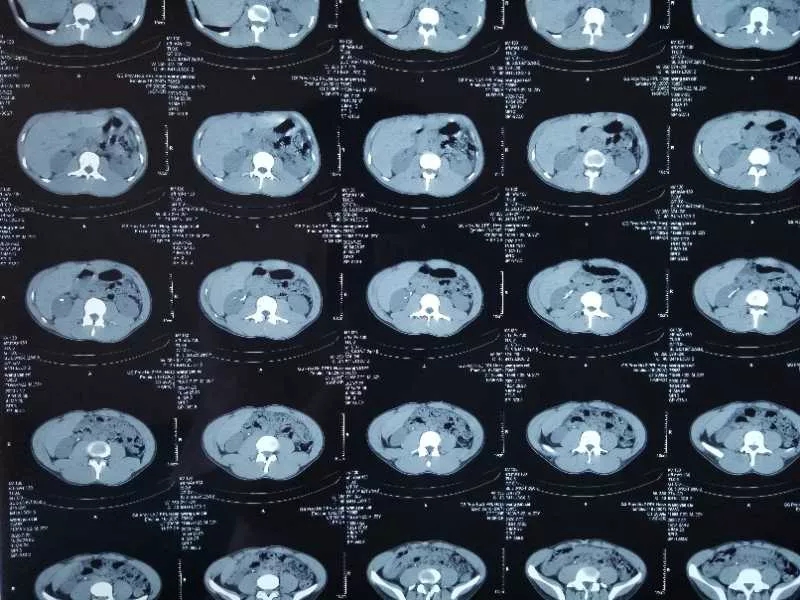

CT提示:右肾结石

行经尿道一次性输尿管软镜钬激光碎石手术,软镜进入右侧肾盂、肾盏内发现结石图像:结石由一层薄的黏膜包裹,故患者在体外冲击波碎石后症状仍不缓解,